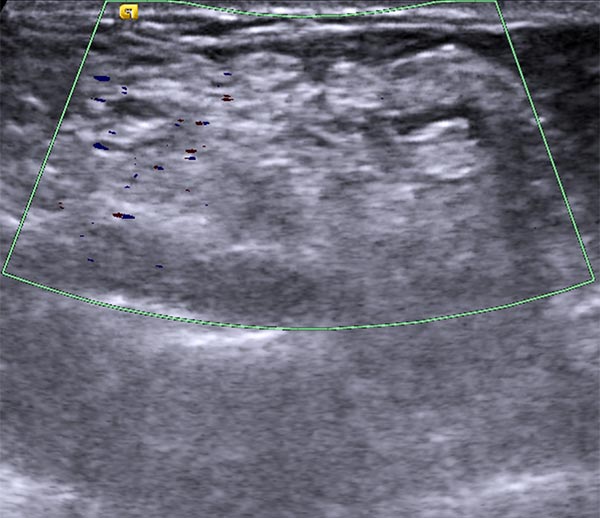

Duplex sonography after multiple sclerotherapy sessions shows almost complete occlusion of the dysplastic venous channels. No more color signals in the now echogenic lesion showing no more open dysplastic venous channels.